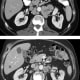

Patients received treatment by IV infusion: 3 mg per kilogram of nivolumab plus 1 mg per kilogram of ipilimumab every three weeks for four doses, followed by a maintenance regimen of 3 mg per kilogram of nivolumab alone every two weeks thereafter. The patients were enrolled between December 2016 and October 2017. Two of the 15 men (13 percent) experienced a significant drop in PSA – by at least 50 percent. “More encouragingly,” notes Antonarakis, “one-quarter of patients achieved an objective response, meaning that their tumors shrank partially or completely. These responses were durable and typically lasted more than nine to twelve months.” But here’s the most exciting part: At least two of these patients were still alive more than 18 months later – which means that Antonarakis and Luo don’t even know how long the response will last, because it’s still happening.